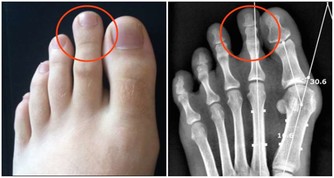

動物肝臟中含有豐富的鐵元素,是個補血的佳品,除了其中會含有豐富的鐵元素,還含有大量的蛋白質、維生素A、維生素B族、鋅等營養物質。除此之外,動物肝臟還含有大量嘌呤成分,嘌呤進入體內後要進行新陳代謝,其最終產物是尿酸。尿中尿酸排出過多可形成尿酸結石。